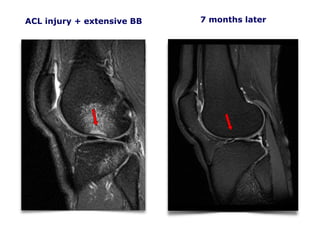

ACL injury + extensive BB

CKC MRI 110206

7 months later

Conclusion:

A majority of

acutely ACL injured

knees (92%) had a

cortical depression

fracture, which was

associated with larger

BME volumes.

This indicates strong

compressive forces

to the articular

cartilage at the time

of injury, which may

constitute an

additional risk factor

for later knee OA

development.

CKC UK